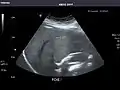

Left kidney

Kidneys: Right and left kidneys measure 11.5 cm and 12 cm in length respectively. No hydronephrosis. Small left lower pole kidney cyst.